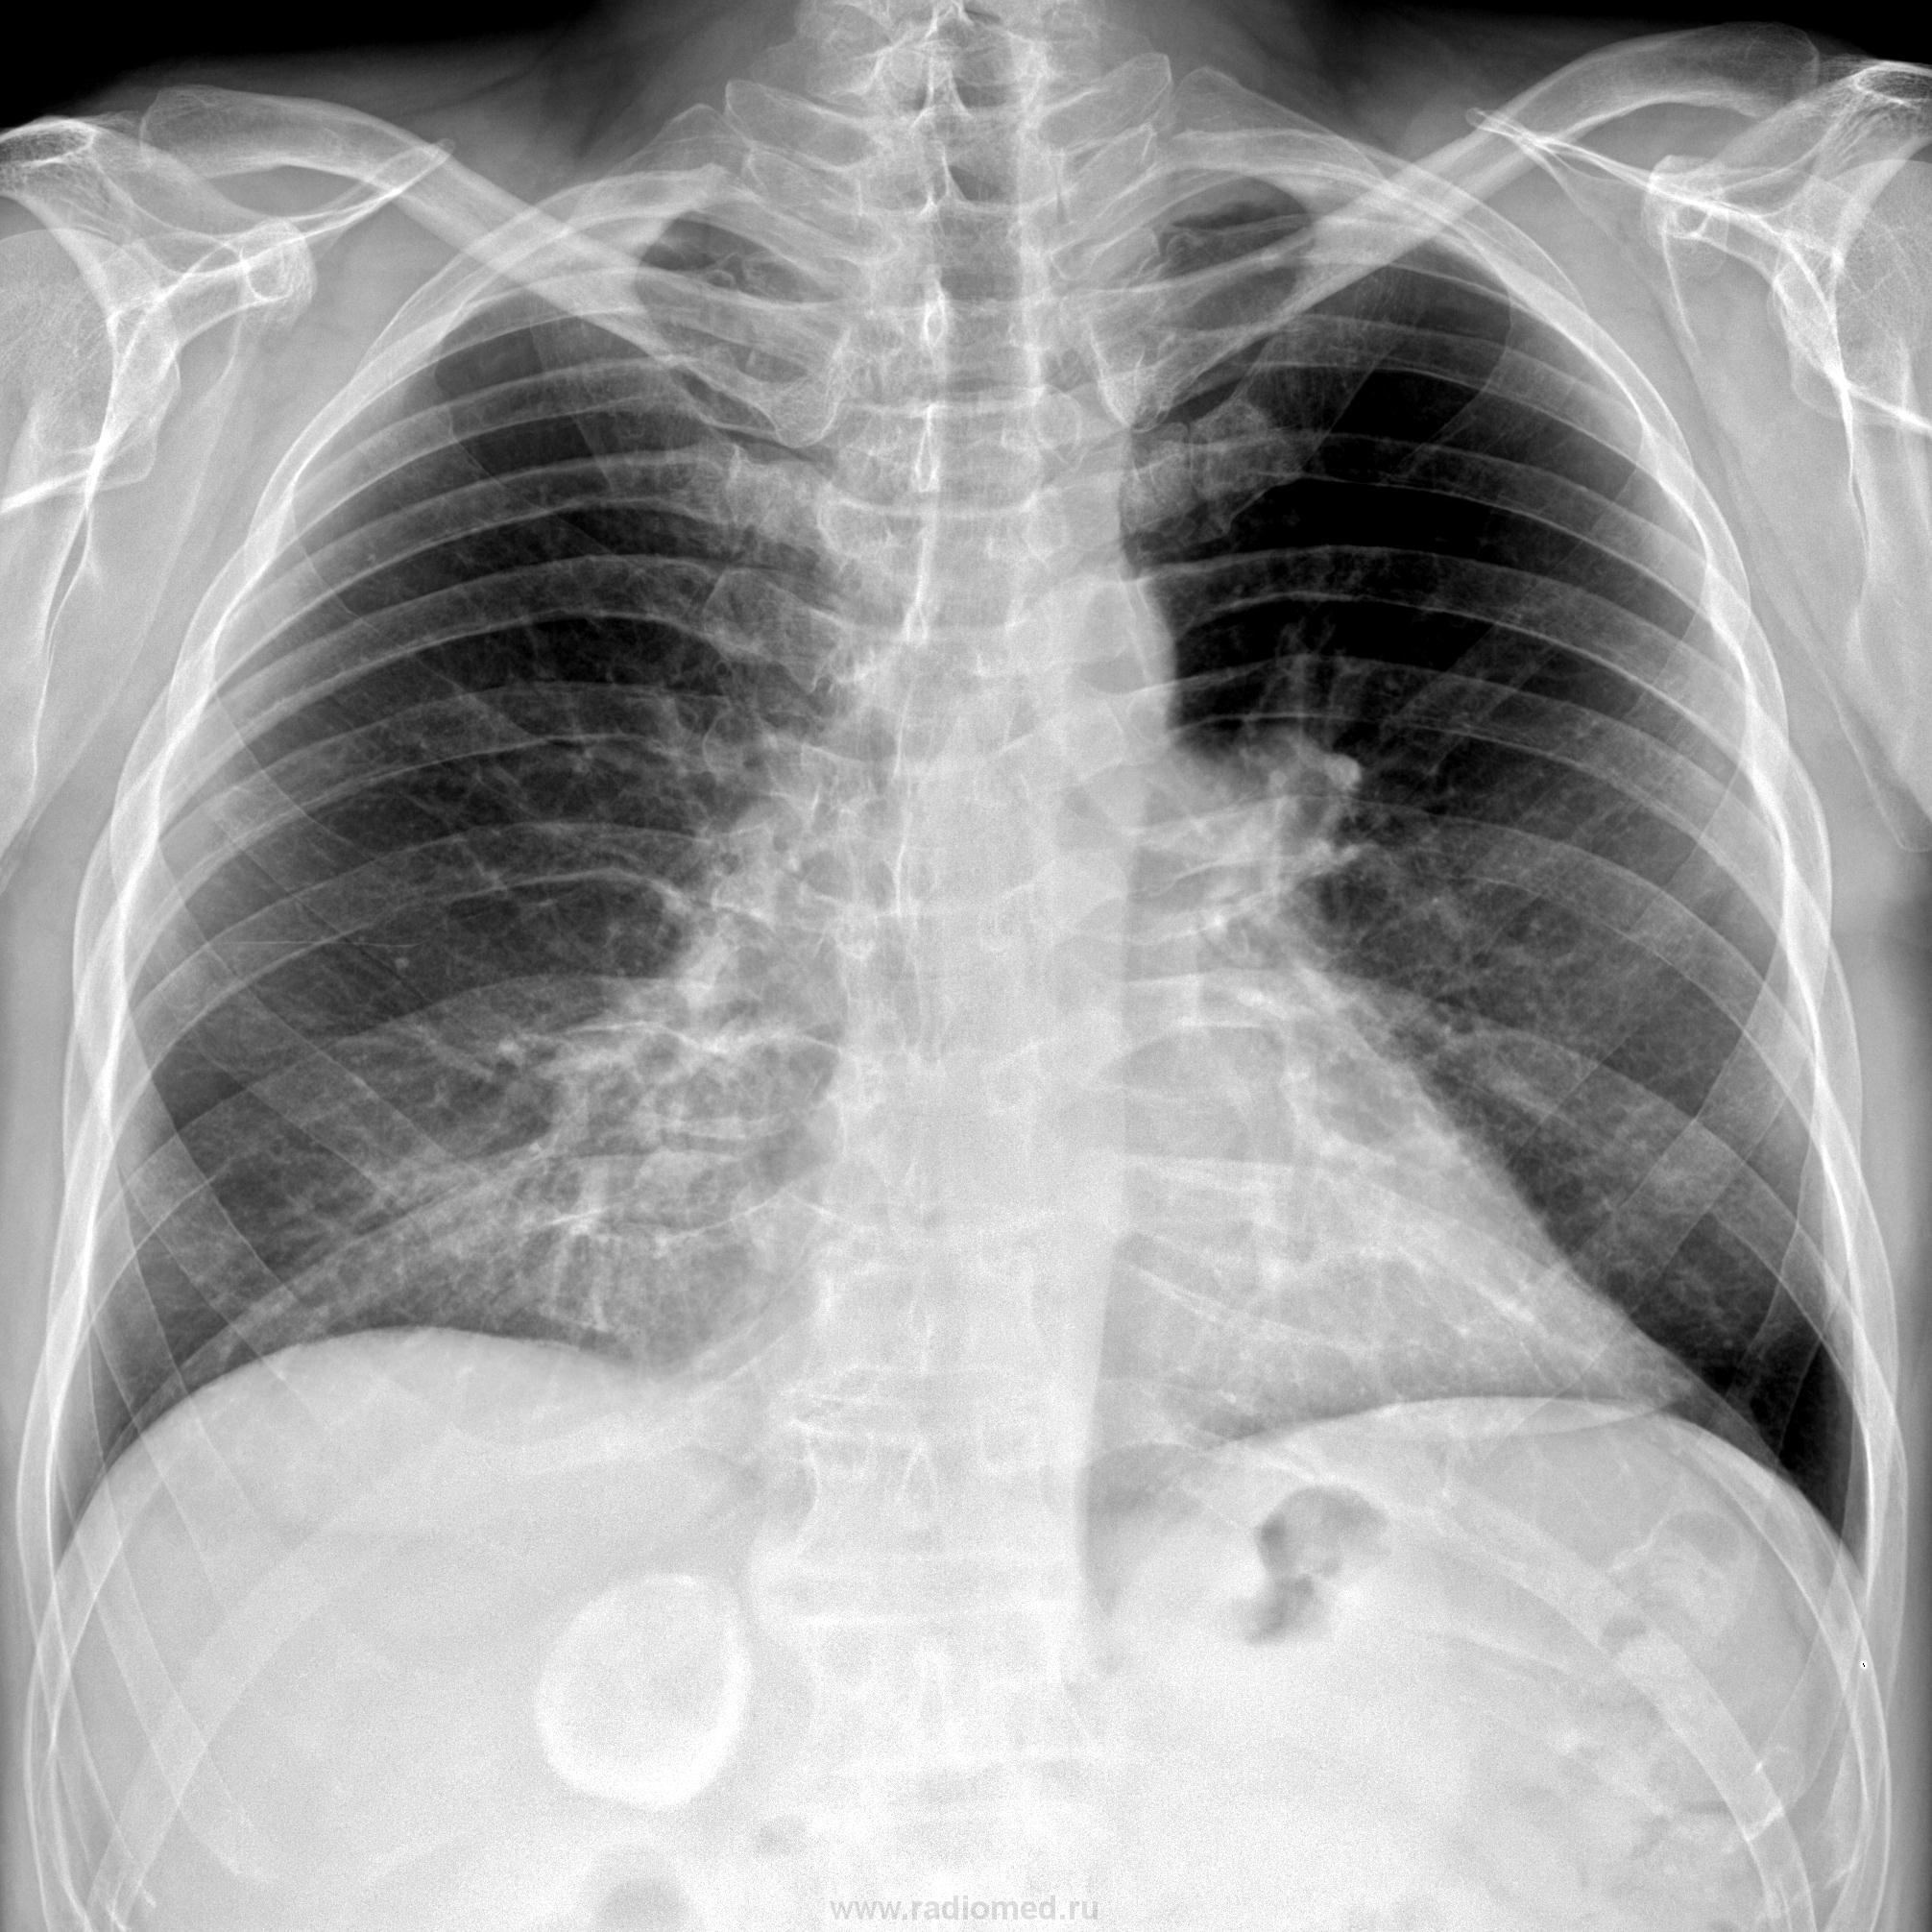

Пациент 1966 г.р. перенес ОРЗ неделю назад с кашлем и субфебрильной Т. По прямому предположила пневмонию. А на боковом- есть ли изменения? подскажите. А еще-что за округлая тень справа в брюшной полости?

Не вижу пневмонии. Эхиноккок?

Предположу заболевание почки-надпочечника. УЗИ по -любому. Пневмонии как-то не видно.

Это может быть и огроменный камень в желчном пузыре. Пневмонии нет.

В проекции   6-7 сегмента печени-  округлая тень   эхинококковой   кисты с обызветствленными стенками  . Да- на  УЗИ печени и-  что там еще делают ? Антитела к эхинококку , кажется ,  исследуют .

Оценил бы как уплотнение легочного рисунка, за счет диффузного пневмофиброза. Норма.

Поскольку архива у нас нет, есть только новые одни негативы, я заключил бы остаточные изменения справа в средней доле. И Никто с этой версии меня не подвинет.))

Скорее с Вашими свежими изменениями.Впрочем, назначаем динамику через месяц и станет яснее.

Пока сказал бы "фаза неполного рассасывания".А там видно будет.

Только не надо фаз, стадий и т.д..  Просто - какой-то неуточненный участок уплотнения и все. Типа "Справа  в средней доле линейный участок уплотнения". Про пневмонию - это к терапевту ему решать и отвечать, и не забудем, что рентгенкартина отстает от клиники, терапевт говорит - здоров, а по снимку еще что-то есть.